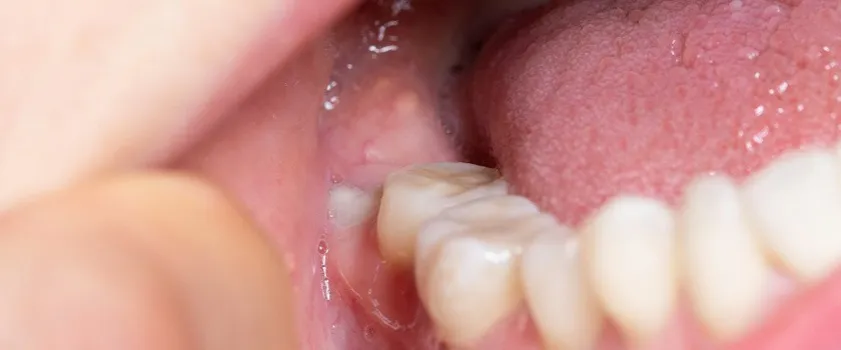

Często zdarza się, że ząb mądrości wyrzyna się tylko częściowo. Między koroną zęba a dziąsłem tworzy się wtedy niewielka kieszonka. Jest to idealne miejsce dla resztek jedzenia i bakterii, które łatwo tam zalegają i są trudne do usunięcia podczas codziennego szczotkowania. Gromadzenie się drobnoustrojów prowadzi do stanu zapalnego, zwanego zapaleniem okołokoronowym. Objawia się ono bólem, obrzękiem, zaczerwienieniem dziąsła, a czasem nawet ropną wydzieliną. W takiej sytuacji kluczowa jest wzmożona higiena i często konieczna jest interwencja stomatologiczna.